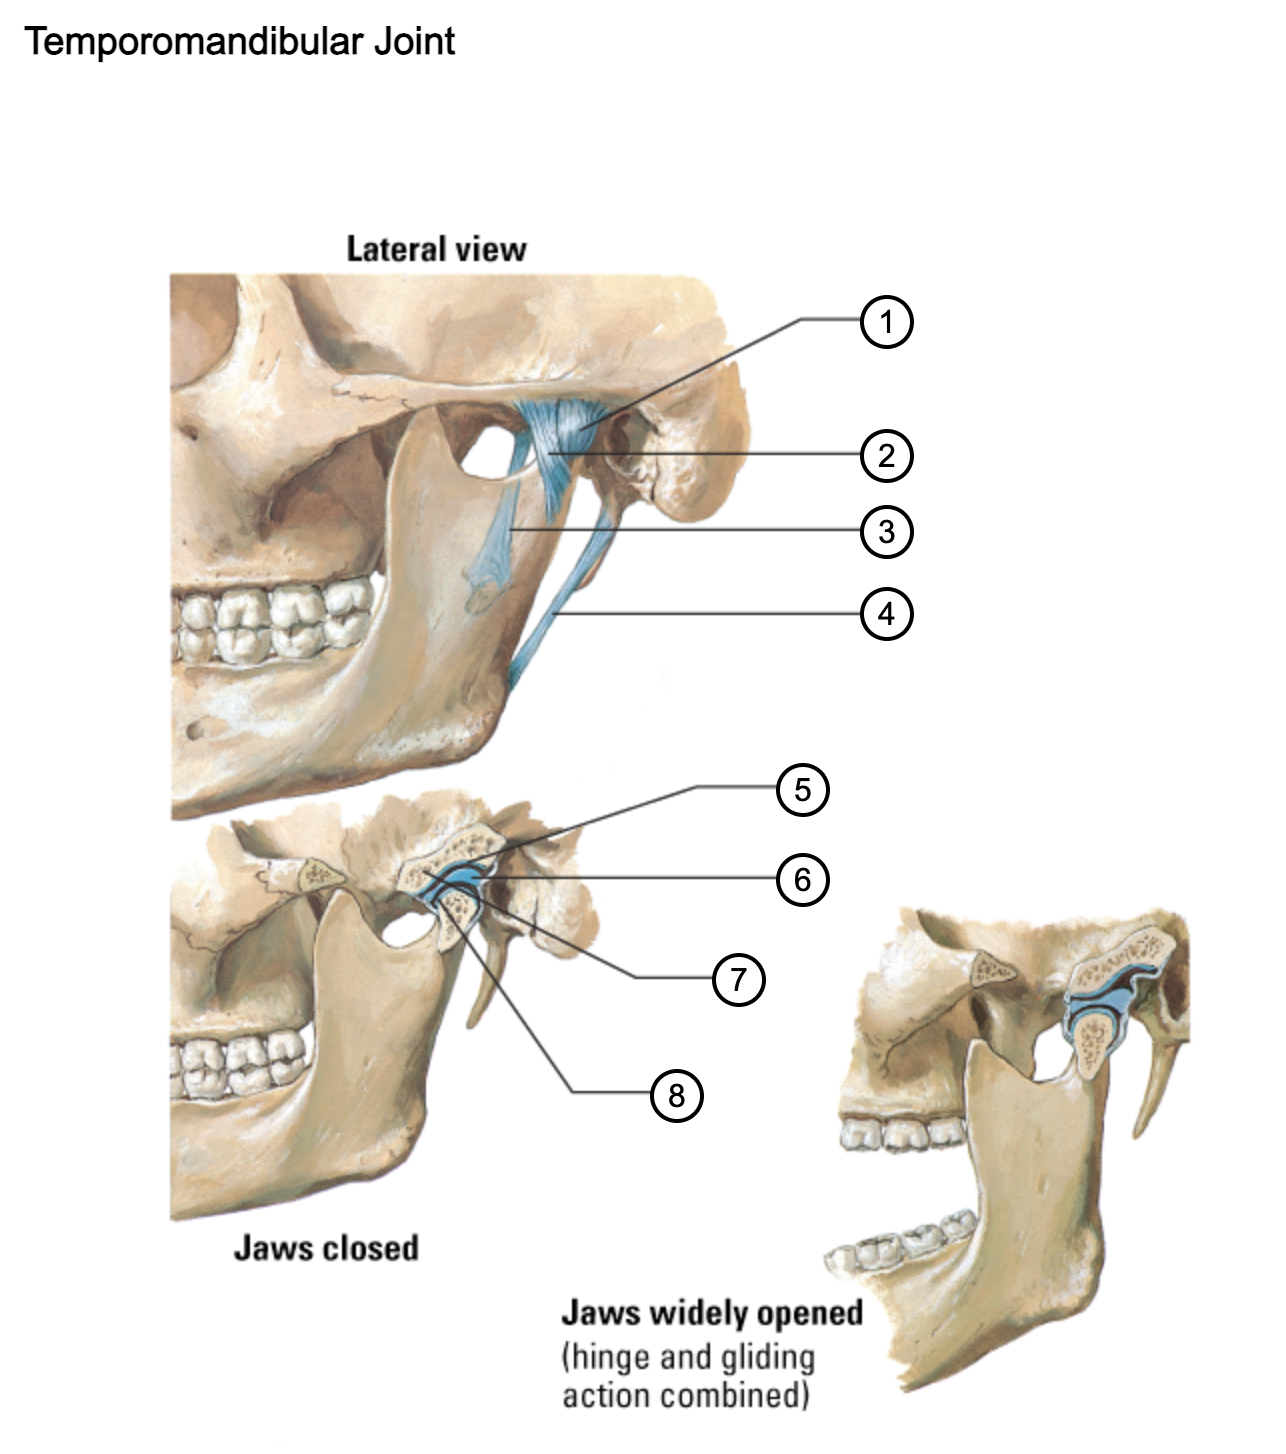

1

capsule of temporomandibular joint

2

lateral temporomandibular ligament

3

sphenomandibular ligament

4

stylomandibular ligament

5

mandibular fossa

6

articular disc

7

articular tubercle

8

capsule of temporomandibular joint